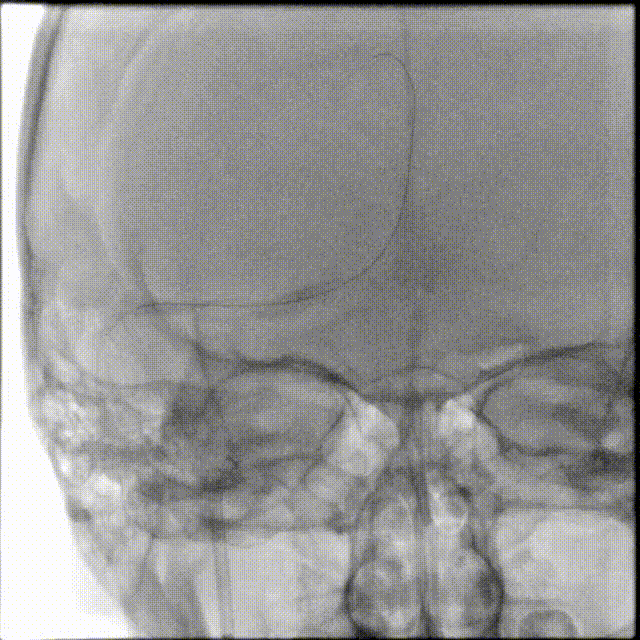

术前CTA/CTP检查,动脉成像未见明显异常,平扫CT可见右侧横窦区域高密度、左侧顶叶片状高密度,窦汇区域、上矢状窦区域高密度充盈。随后紧急性头颅MRV检查,MRV提示上矢状窦及右侧横窦区域不显影。

图注1:1A/1B 平扫CT可见右侧横窦、窦汇区域高密度,额顶叶片状高密度灶

1C 通路CTA检查动脉像未见特殊

1D/1E MRV冠状位及侧位可见上矢状窦及右侧横窦消失,左侧横窦乙状窦部分显影